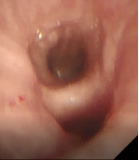

接受新疗法的患者两年前就明确诊断为慢阻肺,之后长期吸入大剂量信必可治疗,但咳痰和气急的症状仍控制不佳,本次入院复查发现肺功能明显下降,为中度阻塞性通气功能障碍。4月15日,王昌惠主任、李萍主任医师和李譞主治医师运用冷冻喷雾技术,成功完成COPD患者的支气管粘膜消融手术,术后患者无不良反应发生,第二天即顺利出院。症状得到明显改善,患者对王昌惠教授团队的感激之情溢于言表。

王昌惠教授表示,纤毛功能障碍、黏液高分泌、细菌定植增加、气道炎症与氧化应激等均为慢阻肺发病的重要机制,近几年随着支气管镜介入技术的不断进步, 非药物治疗方式的液氮计量冷冻喷雾成为研究热点。团队的研究和实践均提示,冷冻喷雾消融治疗可以促进支气管粘膜上皮再生,减少杯状细胞的数量,改善纤毛的运动,进而提高COPD患者的生活质量,同时冷冻治疗具有并发症少、恢复快、不易形成瘢痕组织导致气道狭窄等优势,是COPD患者治疗的新希望,也是团队今后继续努力探索的方向。

术前支气管 术中改变 术后支气管